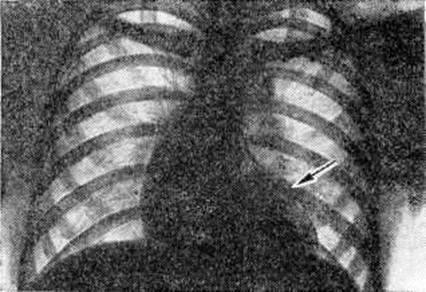

Диагноз. При аортальном стенозе данные векторкардиографии (смотри полный свод знаний) отражают подъём левожелудочкового давления лучше, чем ЭКГ. Только заметное повышение давления (градиент давления на уровне сужения более 60 миллиметров ртутного столба) приводит к появлению на ЭКГ признаков гипертрофии левого желудочка. У новорождённых на ЭКГ могут быть лишь признаки гипертрофии правого желудочка. Характерные клинические, симптомы в сочетании с признаками гипертрофии левого желудочка на ЭКГ указывают на выраженный аортальный стеноз (рисунок 3). При рентгенологическое исследовании у детей тень сердца нормальных размеров или с признаками гипертрофии левого желудочка. При высоком конечно-диастолическом давлении в левом желудочке и левом предсердии отмечаются застойные явления в прикорневых отделах лёгких. Может быть расширена восходящая часть аорты (постстенотическая дилатация). У детей с выраженным стенозом рентгенологически определяется аортальная конфигурация сердца (рисунок 4) и усиленный легочно-сосудистый рисунок. При ретроградной катетеризации сердца катетер проводят через место сужения в полость левого желудочка, измеряют градиент давления, выявляют место сужения и возможные сопутствующие пороки. У новорождённых и грудных детей катетеризация сердца может быть заменена эхокардиографическим исследованием (смотри полный свод знаний: Эхокардиография). У больных с асимметричной перегородочной гипертрофией во время систолы происходит смыкание передней створки левого предсердножелудочкового (митрального) клапана с гипертрофированным миокардом. Сужение может сопровождаться большим градиентом давления. При нагрузках, приёме сердечных гликозидов или инотропных средств и нитроглицерина градиент давления возрастает, но снижается при использовании р-адреноблокаторов (анаприлина, обзидана, индерала). Во время систолы, следующей после экстрасистолы, артериальное давление уменьшается, в то время как при других видах аортальногостеноза оно возрастает. При массивной мышечной гипертрофии возникает обструкция выходного отдела левого желудочка, нарушается функция митрального клапана. Признаки заболевания аналогичны таковым при других видах аортального стеноза, однако на ЭКГ всегда регистрируют выраженную гипертрофию левого желудочка, удлинение интервала Q — Г, изменения S — Г, зубцов Т и Q. Диагноз может быть установлен достаточно точно с помощью эхокардиографии. Во время катетеризации сердца на киноангиокардиограмме (смотри полный свод знаний: Ангиокардиография) в боковой проекции видно сужение полости левого желудочка в его выходной части. Детей с сердечной недостаточностью оперируют по жизненным показаниям. Так называемый плановые операции при аортальном стенозе выполняют, если в покое градиент давления на уровне сужения выше 60 миллиметров ртутного столба. Аортальную вальвулотомию производят либо по закрытой методике (через верхушку сердца в аорту последовательно проводят вальвулотом и дилататор), либо на «открытом» сердце в условиях умеренной гипотермии (общей или краниоцеребральной) при пережатых полых венах. Доступ — через стенку аорты. В течение 3—5 минут рассекают клапан по комиссурам. Безопаснее устранять порок в условиях искусственного кровообращения. Наибольшие трудности возникают при коррекции надклапанного сужения с гипоплазией аорты, что требует вшивания заплаты в стенку аорты, иногда с протезированием клапанов сердца (смотри полный свод знаний), и асимметричной гипертрофии миокарда. Иссечение мышечных масс может быть выполнено из аортального доступа, который иногда приходится дополнять рассечением стенки левого желудочка. Существуют методики, предусматривающие иссечение миокарда со стороны правого желудочка. К более радикальным операциям относится иссечение миокарда через левое предсердно-желудочковое отверстие с последующим протезированием митрального клапана. Ок. 10% неоперированных детей раннего возраста имеют явные признаки левожелудочковой недостаточности. В течение первого года жизни (особенно первого месяца) большая их часть погибает. У выживших со средней степенью сужения клинические, признаки Пороки сердца врождённые с возрастом нарастают. Страдающие тяжёлой формой стеноза в 1—7% случаев умирают внезапно. В 20% случаев при стенозе развивается регургитация. При асимметричной гипертрофии перегородки сердца продолжительность жизни ограничена 40—50 годами. Результаты оперативного лечения во многом определяются исходной степенью тяжести стеноза, его морфологией, состоянием миокарда левого желудочка, радикальностью оперативного вмешательства и отсутствием послеоперационной недостаточности клапана. Операционная летальность не превышает 10%. Через 10 лет около 25% оперированных нуждается в повторном вмешательстве для ликвидации рестеноза или регургитации. Во время повторных операций, как правило, производят протезирование клапана. У остальных отдалённые результаты хорошие и удовлетворительные: большая часть из них может считаться практически здоровыми. Аортолёгочный свищ — врождённое соустье между восходящей частью аорты и лёгочным стволом — относится к редким аномалиям (0,3% всех врождённых пороков «сердца.). На 8-й неделе у эмбриона формируется спиральная перегородка, которая при нормальном развитии делит общий артериальный ствол на два продольных канала (аорту и лёгочный ствол) и срастается в области их фиброзных колец с межжелудочковой перегородкой. Нарушения механизма образования перегородки приводят к появлению патологический отверстия между двумя магистральными сосудами. В большинстве случаев дефект располагается на 1—5 миллиметров выше фиброзного кольца устья аорты. Реже отверстие достигает клапанов аорты и лишь иногда располагается в дистальной х/3 восходящей части аорты. Размеры соустья варьируют широко — от 2 до 30 миллиметров. Отсутствие межсосудистой перегородки от клапанов аорты до дистального отдела восходящей части аорты может рассматриваться как общий артериальный ствол. Характер гемодинамических нарушений при аортолёгочном свище во многом сходен с расстройствами кровообращения при открытом артериальном протоке. Однако вследствие близости патологический отверстия к устью аорты (отверстие аорты) осложнения развиваются быстрее, в частности лёгочная гипертензия. Клиническая картина определяется размерами аортолёгочного свища и состоянием сосудов лёгких. При небольших размерах свища (менее 5 миллиметров) течение порока аналогично таковому при артериальном протоке. Однако эпицентр систолодиастолического шума при этом пороке располагается ближе к средней линии во втором межреберье у грудины. При средних размерах свища (6—10 миллиметров) клинические, проявления более тяжёлые, чем при артериальном протоке такого же диаметра. Отмечается бледность, ребёнок отстаёт в физическом развитии, у него легко возникает одышка, даже при небольших физических нагрузках; характерны слабость, повышенная утомляемость. Большой свищ (более 10 миллиметров) сопровождается высокой лёгочной гипертензией, поэтому возникновение цианоза, приступов одышки, нарушений ритма (вначале лишь при нагрузках) свидетельствует о выравнивании давления в аорте и лёгочном стволе и двустороннем шунтировании крови. В этот период может проявиться сердечная недостаточность. До развития лёгочной гипертензии (при малых и средних размерах свища) клинические, признаки порока во многом совпадают с проявлениями артериального протока (систолодиастолический шум, дрожание над сердцем и другие). При развитии лёгочной гипертензии вначале исчезает диастолический шум, а затем ослабевает и систолический. На ЭКГ в зависимости от степени нарушений гемодинамики определяются признаки перегрузки левого, обоих или преимущественно правого желудочка, нарушения сердечного ритма (пароксизмальная тахикардия, экстрасистолия). При рентгенологическое исследовании — изменения размеров сердца и сосудов лёгких взаимосвязаны с величиной и направлением сброса крови. При большом артериовенозном сбросе увеличены основание и левые отделы сердца, усилен лёгочный рисунок, выбухает дуга лёгочного ствола; при сбалансированном шунте наблюдается гипертрофия обоих желудочков, обеднение сосудистого рисунка по периферии лёгких. Катетеризация и контрастирование сердца являются основными методами распознавания порока и установления степени нарушений гемодинамики. Катетер, проведённый из правого желудочка в лёгочный ствол, может попасть через свищ в аорту. В зависимости от величины давления в аорте и лёгочном стволе контрастирование одной из них может дать полное представление о локализации, размерах, направлении и объёме шунта. Для этой цели производят аортографию (смотри полный свод знаний) в прямой и правой косой позиции (с помощью катетера, проведённого ретроградно до клапана аорты). Величина сброса крови может быть установлена также исследованием её на насыщение кислородом в различных участках правых отделов сердца и лёгочном стволе красочными, платиноводородными и термодилюционными пробами. Порок следует дифференцировать с открытым артериальным протоком (смотри полный свод знаний), дефектом межжелудочковой перегородки, стенозом лёгочной артерии, стенозом устья аорты, недостаточностью митрального клапана, разрывом аневризмы синуса Вальсальвы, аневризмами коронарных сосудов, артериовенозными аневризмам левой внутригрудной, межрёберных артерий или перикардиальных сосудов. Лечение оперативное, за исключением больных с выраженной лёгочной гипертензией и преобладающим венозно-артериальным сбросом крови (им показано ограничение в физических нагрузках и терапия сердечной недостаточности). Для закрытия свища существует несколько способов. Свищ, расположенный выше аорты и клапанов лёгочного ствола, перевязывают несколькими лигатурами. Если свищ прилегает к клапану аорты, то его можно ушить со стороны лёгочного ствола (рисунок 5) в условиях умеренной гипотермии с выключением сердца из кровообращения. В большинстве же случаев операция при аортолёгочном свище проводится в условиях искусственного кровообращения. В зависимости от размеров отверстия и продолжительности операции применяется один из видов защиты миокарда (холодовая или медикаментозная кардиоплегия, коронарная перфузия и тому подобное). При дистально пережатых сосудах производят либо ушивание свища, либо вшивание заплаты (что предпочтительно) со стороны аорты или лёгочного ствола. Неоперированные больные с лёгочной гипертензией обычно погибают в детском возрасте. Летальность после операций у больных без выраженной лёгочной гипертензии не превышает 5%, у больных с лёгочной гипертензией более 50%. Результаты в отдалённые сроки после операции в подавляющем большинстве случаев благоприятные. Артериальный проток соединяет аорту с лёгочным стволом. Необходимый в период эмбрионального развития для нормального кровообращения, после рождения ребёнка он облитерируется. Если облитерация не наступает, развиваются нарушения гемодинамики, сброс крови из аорты в лёгочный ствол. Лечение оперативное (смотри полный свод знаний: Артериальный проток). Атрезия лёгочного ствола в сочетании с дефектом межжелудочковой перегородки представляет собой одну из форм тетрады Фалло. Обычно наблюдается гипоплазия правого желудочка (I тип); возможно сочетание нормального или даже расширенного правого желудочка с несостоятельностью трёхстворчатого клапана (II тип). Клапан лёгочного ствола маленький, заращён. Дистальнее его ствол сосуда сохранен. Центральный кровоток осуществляется через дефект перегородки в левые отделы сердца и аорту, далее через артериальный проток в сосуды лёгких. Артериальный проток обычно узкий. Степень цианоза зависит от величины сброса крови через артериальный проток. Цианоз заметен с момента рождения, усиливается с развитием сердечной недостаточности; наблюдаются приступы гипоксии, ацидоз. На ЭКГ отмечаются признаки преобладания левого желудочка, особенно при I типе порока. Рентгенологические исследование выявляет увеличение размеров сердца, лёгочно-сосудистый рисунок ослаблен. При контрастировании сердца виден правый желудочек с выходным отделом в виде слепого мешка и регургитацией в предсердие. Этот порок нужно дифференцировать с трикуспидальной атрезией, тетрадой Фалло, стенозом лёгочного ствола, транспозицией крупных сосудов со стенозом лёгочного ствола. Лечение оперативное. Если правый желудочек недоразвит, то целесообразно наложить межсосудистый анастомоз; если он развит нормально, то производят лёгочную вальвулотомию. В некоторых случаях между правым желудочком и лёгочным стволом вшивают кондуит (консервированный в глутаровом альдегиде биологический трансплантат клапана сердца, вшитый в сосудистый протез). Послеоперационная летальность у новорождённых с гипоплазированным правым желудочком высокая (до 80%). Без операции практически все дети погибают в течение первого года жизни. Атрезия устья аорты сочетается с гипоплазией восходящей части аорты, гипоплазией или атрезией левого желудочка и атрезией или выраженным стенозом митрального клапана. Устья коронарных артерий, как правило, располагаются в луковице аорты. Для поддержания жизни необходимы артериальный проток и дефект межпредсердной перегородки (открытое овальное окно). Кровообращение при этом происходит следующим образом: венозная кровь большого и малого круга кровообращения смешивается в предсердии, поступает в правый желудочек, лёгочный ствол и через артериальный проток в аорту. Аортальная атрезия и другие варианты гипоплазии левых отделов сердца являются самой частой причиной смерти новорождённых с Пороки сердца врождённые Хотя при рождении ребёнок может выглядеть нормально, вскоре выявляется сердечная недостаточность с дилатацией правого желудочка, падением АД и цианозом. Данные физикального, электрокардиографического и рентгенологическое исследований далеко не всегда позволяют правильно распознать порок. Только эхокардиография, катетеризация сердца и киноангиокардиография дают возможность поставить окончательный диагноз и оценить гемодинамические нарушения. Порок считается неизлечимым, оперативное вмешательство не проводится. Большая часть новорождённых с этой патологией погибает в течение нескольких дней после рождения. Атриовентрикулярный канал (неполная форма) представляет собой сочетание первичного дефекта межпредсердной перегородки с расщеплением створки митрального или трёхстворчатого клапана или створок обоих клапанов. Первичный дефект межпредсердной перегородки всегда большой, имеет полулунную форму, сверху отграничен межпредсердной перегородкой, снизу фиброзным кольцом клапанов. Передняя створка митрального клапана расщеплена обычно в середине общей части фиброзного кольца клапана. Аналогично может быть изменена и перегородочная створка трёхстворчатого клапана.. Нарушения гемодинамики аналогичны таковым при первичном дефекте межпредсердной перегородки. Расщепление створки клапана приводит к регургитации крови из желудочка (или обоих желудочков) в оба предсердия; степень регургитации может быть различной. Для детей в возрасте до 3 лет при этом пороке характерна сердечная недостаточность, которая сопровождается одышкой, низкой толерантностью к физическим нагрузкам, резким отставанием в развитии ребёнка. У взрослых, как правило, наблюдаются хронический недостаточность кровообращения, приступы пароксизмальной тахикардии, присоединяется инфекционные эндокардит. Основные физикальные признаки порока: бледность кожи, «сердечный горб», интенсивный систолический шум над верхушкой сердца, расщепленный 11 тон над лёгочным стволом. На ЭКГ выявляются неполная блокада правой ножки пучка Гиса, отклонение электрической оси влево при наличии диастолической перегрузки правого желудочка; на ФКГ — интенсивный систолический шум над верхушкой сердца, расщепление II тона с усилением лёгочного компонента. Рентгенологически отмечается увеличение обоих желудочков, нередко кардиомегалия. При катетеризации сердца обнаруживают низкий дефект межпредсердной перегородки и регургитацию из желудочка при заполнении его контрастным веществом. Лечение — оперативное: из правосторонней торакотомии (смотри полный свод знаний) или срединной стернотомии (смотри полный свод знаний: Медиастинотомия) в условиях искусственного кровообращения расщепленную створку клапана соединяют отдельными П-образными швами, стремясь не сузить клапан. Дефект межпредсердной перегородки закрывают заплатой.